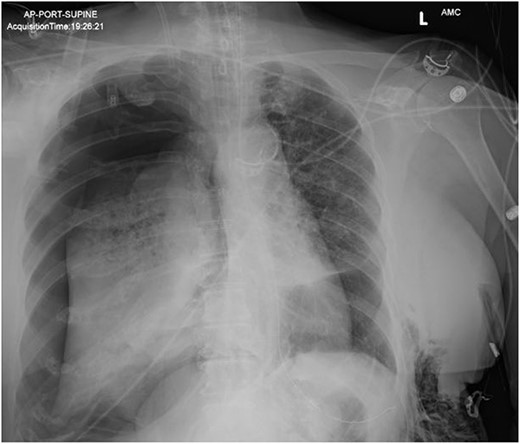

On Hospital Day 2, an interval CXR showed continued resolution of the right-sided pneumothorax but worsening subcutaneous emphysema of the bilateral chest wall and pneumoperitoneum (Fig. 3). Surgical consultation was sought, leading to diagnostic laparoscopy. In the abdomen, emphysematous changes within the gastrohepatic ligament and omental adhesions to the anterior abdominal wall were visualized (Figs 5 and 6). Laparoscopic exploration revealed no diaphragmatic injury or perforated viscera but identified emphysematous changes throughout the preperitoneal space, small and large bowel mesentery, and right paracolic gutter (Figs 7 and 8). Immediate post-op CXR no longer showed evidence of pneumoperitoneum (Fig. 4). The patient was transferred back to the ICU and extubated after three days on Day 5. After the removal of chest tube and transfer to a medical floor on Day 8, the patient developed aspiration pneumonia that was treated with antibiotics. She was discharged on Day 15.

Post-operative chest radiograph showing increased diffuse subcutaneous emphysema in chest, lower neck and upper left abdominal wall. Previously demonstrated pneumoperitoneum is not visualized on the current film.